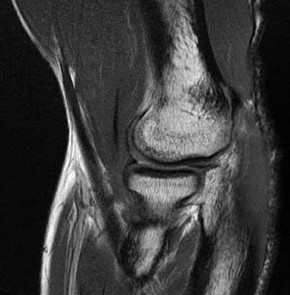

CLINICAL SITUATION FOR QUESTIONS 22 THROUGH 25

A 22-year-old man sustains an injury to his right knee in a motor vehicle collision. Figure 22a is the posterior stress radiograph of the involved knee, and Figure 22b is a selected MR image that identifies the injured structure.

The stress radiographs demonstrate posterior instability of the right knee in flexion. The MR images demonstrate injury to both the anterior and posterior cruciate ligament (PCL), with the stump identified with the arrow on the MR image (Figure 22b). The PCL has 2 functional bands. The anterolateral bundle originates from the roof of the intercondylar notch. It runs in a posterolateral direction onto the tibial crest between the posterior attachment of the medial and lateral menisci. During a double-bundled posterior ligament reconstruction, the

anterolateral bundle is tensioned with the knee in a position of mid flexion. The posteromedial bundle has a variable pattern of tension both in extension and in high flexion. Tensioning of the posteromedial bundle in extension may contribute to resistance against knee hyperextension.

The meniscofemoral ligaments are variably present. Although 93% of knees have been reported to have at least 1 meniscofemoral ligament present, both ligaments are simultaneously present in approximately 50% of knees. The ligament of Humphrey (anterior meniscofemoral ligament) and ligament of Wrisberg (posterior meniscofemoral ligament) are delineated by their anatomic relationship to the posterior cruciate.